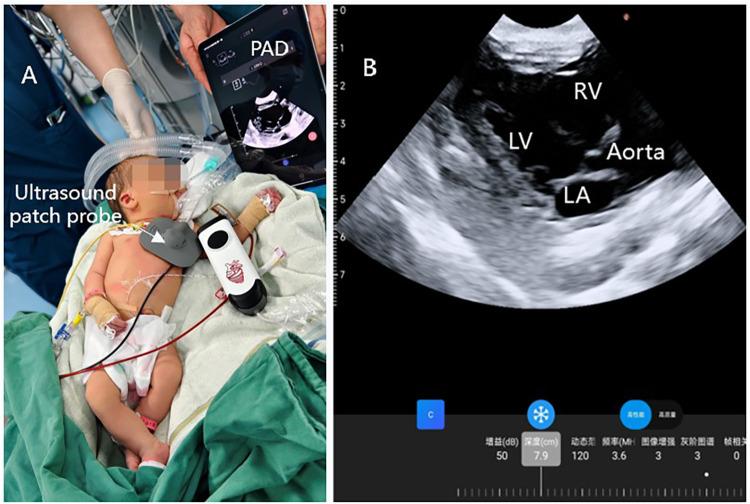

Neonates in the early stage are in the transition from fetal to adult circulation, accompanied by complex hemodynamic changes, which are prone to aggravate the condition of the circulatory system during the perioperative period. Here, we present a case of a 3-day-old neonate with upper gastrointestinal bleeding caused by multiple esophageal and gastric ulcers. To achieve accurate circulation management, we utilized a novel wearable ultrasound device for non-invasive, continuous echocardiographic monitoring throughout general anesthesia gastroscopy and postoperative NICU care. The case demonstrates the feasibility of continuous echocardiographic monitoring in neonates and offers new ideas for circulatory monitoring and management in critical neonates.

早期新生儿正处于从胎儿循环向成人循环的过渡阶段,伴随着复杂的血流动力学变化,这在围手术期容易加重循环系统状况。在此,我们报告一例3日龄新生儿因多处食管和胃溃疡导致上消化道出血的病例。为实现精确的循环管理,我们在全身麻醉胃镜检查及术后新生儿重症监护病房护理期间,使用了一种新型可穿戴超声设备进行无创、连续的超声心动图监测。该病例证明了新生儿连续超声心动图监测的可行性,并为危重新生儿的循环监测和管理提供了新思路。